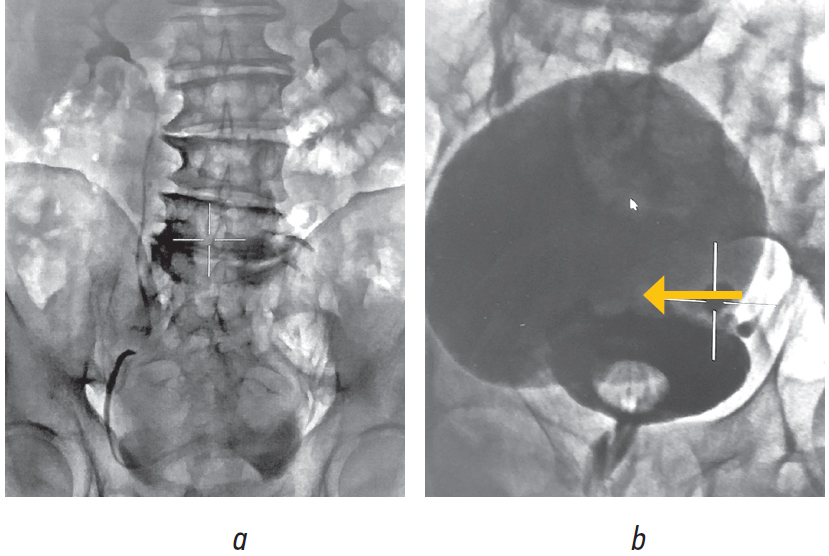

Пациент дообследован (рис. 3, 4). Лабораторные исследования выполнены в стандартном предоперационном объеме. Уровень простатического специфического антигена составил 1,27 нг/мл. При бактериологическом исследовании мочи роста микрофлоры не обнаружено. По данным опросника IPSS — 26 баллов, что соответствует тяжелой симптоматике, качество жизни (QoL) оценено в 4 балла. По данным ультразвукового исследования (рис. 3) объем предстательной железы составил 88 см3, интравезикальная протрузия простаты — Grade III (31 мм); объем мочевого пузыря 300 мл, объем остаточной мочи 132 мл, ДМП объемом 400 мл, опорожняющийся неудовлетворительно (300 мл).

Рис. 3. Ультрасонограмма пациента О., 68 лет: a — гиперплазия предстательной железы, стрелками указана ее «средняя доля»; b — дивертикул мочевого пузыря, указан стрелками / Fig. 3. Ultrasonogram of patient O., 68 years old: a — prostatic hyperplasia, arrows indicate the “middle lobe” of the prostate; b — bladder diverticulum, indicated by arrows

Рис. 4. Результаты обследования пациента О., 68 лет: а — экскреторная урография, выделительная функция почек нормальная; b — нисходящая цистография, определяется дивертикул, превосходящий по объему мочевой пузырь (указан стрелкой) / Fig. 4. The results of the examination of the patient O., 68 years old: a — intravenous urography, the excretory function of the kidneys is normal; b — descending cystography, the diverticulum is determined, exceeding the volume of the bladder (indicated by an arrow)

На основании обследования установлен диагноз: «Доброкачественная гиперплазия предстательной железы. Дивертикул мочевого пузыря». С учетом наличия доброкачественной гиперплазии предстательной железы и большого размера дивертикула с неудовлетворительным опорожнением выполнено хирургическое лечение в объеме: дивертикулэктомия, чреспузырная аденомэктомия. Послеоперационный период протекал гладко. Цистостомический дренаж удален на 10-е сутки после операции, уретральный катетер — на 4-е сутки. После удаления дренажей цистостома зажила, самостоятельное мочеиспускание восстановлено в полном объеме с хорошими уродинамическими показателями.